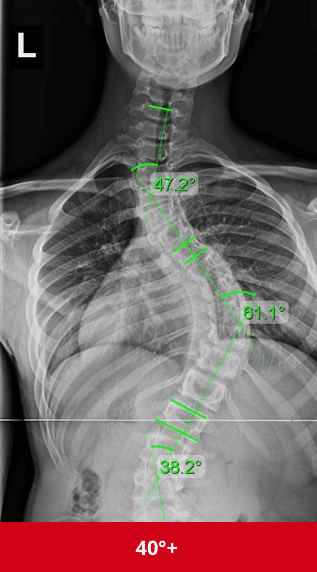

السبب الرئيسي لزيادة الانحناء هو النمو السريع. فعندما يدخل الطفل أو المراهق مرحلة النمو، خصوصًا بين عمر 10 و15 سنة، يبدأ العمود الفقري في التمدد بسرعة، وهنا يمكن أن يتفاقم الانحناء إذا لم تتم المتابعة الصحيحة.

إجراء أشعة متابعة بانتظام لمراقبة زاوية الانحناء (زاوية كوب).

نعم، خصوصًا خلال فترات النمو السريع.

الانحناءات الصغيرة قد تستقر، لكن المتوسطة غالبًا تحتاج علاجًا.

هل الجراحة تصبح ضرورية إذا أهملت العلاج؟

نعم، الإهمال يزيد احتمالات الحاجة للجراحة مستقبلًا.

الاعوجاج حالة مستمرة ولهذا السب قد تحتاج تدخلًا في مراحل مختلفة من العمر. وبفضل وجود تقنيات التصنيف المعتمدة ، يمكن للأطباء تصميم خطة علاجية مخصصة تضمن تدخلاً جراحيًا عند الضرورة أو العلاج غير الجراحي قبل ذلك، لتفادي الاضطراب في الوظائف التنفسية أو أي أعراض متأخرة. فريقنا المحترف يضم نخبة من الأطباء والمتخصصين الذين يجمعون بين الخبرة والاحترافية لتقديم خطة علاجية غيرر جراحيه شاملة ومخصصة لحالتك، تضمن السيطرة على الانحناء ومنع زيادته.